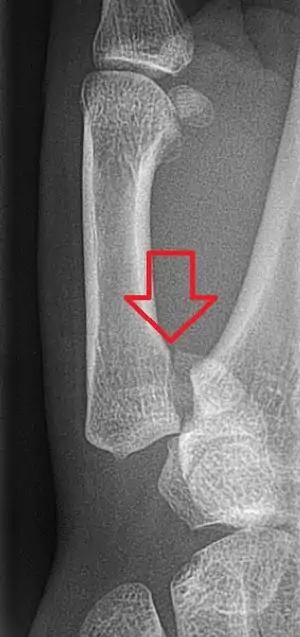

| Toddler's fracture | Toddlers | undisplaced spiral fracture of distal tibia in children under 8 years old | low-energy trauma, often rotational | The toddler's fracture revisited Archived 2016-03-03 at the Wayback Machine at Wheeless' Textbook of Orthopaedics online | ![]() |